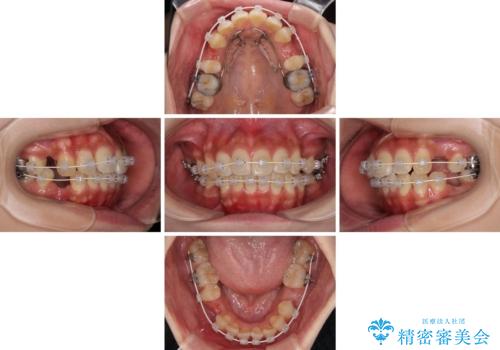

- 審美装置

- 1年11ヶ月

アンカースクリューと補助装置を使用して上顎大臼歯を遠心移動させることで咬み合わせを改善し、更には口元の突出感を改善するために上下左右の小臼歯4本を抜歯し、ワイヤー装置によりデコボコを解消しながら口元の突出感も改善していくこととしました。

上下の前歯が接触する仕上がりとなったので、横顔の印象が大幅に改善されました。